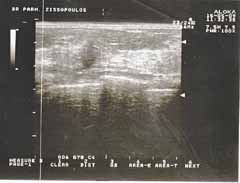

Δρ Παρμενίων Ζησόπουλος

Οι απεικονίσεις των περιστατικών που επιδεικνύονται παρακάτω, έγιναν με κυρτές κεφαλές 3,5 και 5 ΜΗΖ, προκειμένου να φανεί, ότι και με τον εξοπλισμό αυτό, που σιγά-σιγά διαθέτουν όλο και περισσότερα ιατρεία, είμαστε σε θέση να έχουμε ικανοποιητικά αποτελέσματα.

Oι τελευταίες 4 απεικονίσεις έγιναν με ειδικό για μαστό ηχοβολέα linear, εναλλασσομένης συχνότητος 7,5-10ΜΗΖ.